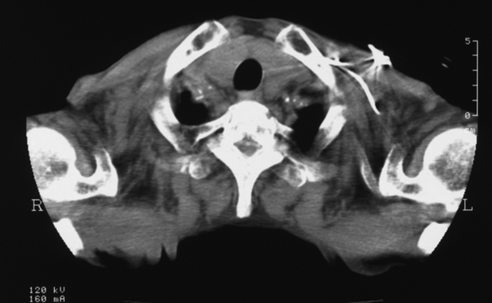

- Age/Sex: 82M

- Chief Complaint: 側傫偲側偔懱偑偩傞偄

- Clinical Course

- 15擭慜 complete AV block偱pacemaker怉偊崬傒

- 嶐擭6寧 COPD偵懳偟偰嵼戭巁慺椕朄

- 嶐擭7寧 寫懹姶弌尰

- 嶐擭8寧 撪壢傊擖堾

- 峛忬態惛嵏偺偨傔I-123峛忬態僔儞僠僌儔僼傿傪梊掕偟偰偄偨偑姵幰偺帠忣偵傛傝戅堾偡傞偙偲偲側偭偨丅

- 戅堾慜偵99mTcO4偵曄峏偟偰峛忬態僔儞僠僌儔僼傿傪巤峴偟偨丅

- Lab. data

- TP:7.8g/dl, T-Bil:1.00mg/dl, ALP:329 IU/L, LAP:66 IU/L,

兞-GTP:114 IU/L, CHE:94IU/L, AST:77.4 IU/L, ALT:40 IU/L,

LDH:140.8 IU/L

- CPK:911IU/L, CPKMB:25.8IU/L

- WBC:3200/兪L, RBC:369枩/兪L, Hb:12.0g/dl, Hct 37.4%, Plt

14.9枩/兪L, CRP 0.1mg/dl

- TSH: 179.76兪U/ml, FT3 0.77pg/ml, FT4 0.66ng/dl,

microsome test 409,600, Anti-TPO Ab >50, Anti-Tg Ab

>100

- Images

- Tc-99m scan: uptake 6.8%

- neck CT